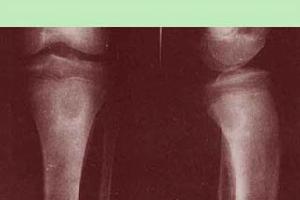

本病多發於青少年,以脛骨下端及上端、橈骨下端等處多見,亦可見於股骨及肱骨。患者多有急性感染史,以後遺留有局限性疼痛。重者可有紅熱、腫脹等局部表現,但少有嚴重者。一般無全身症狀可有間歇期,並呈急性發作。

局限性骨膿腫患者表現為局部隱痛、腫、熱,有時毫無不適。一旦體質差,可局部急性發作。X片示乾骺端囊樣破壞區,周圍骨質硬化,直徑1~7cm不等,有時在病灶內可能有小死骨碎片。經抗生素治療和休息可好轉,但不能根治,易復發。

本疾病多發生於青壯年,多見於脛骨上端,股骨下端和上端、肱骨上端等長骨兩端。本病主要是由於感染引起,故注意平時的體育鍛鍊,增加身體的抵抗力,有利於本病的預防。